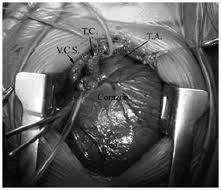

El corazón en la cavidad torácica, su forma es la de una pirámide triangular. El corazón es de contextura firme y de coloración rojiza. El peso del mismo aumenta gradualmente con la edad un poco mayor en el hombre que en la mujer.

Las aurículas están situadas por detrás de los ventrículos podemos describir a dos aurículas una derecha y otra izquierda. Aurícula Derecha: de forma ovoide irregular y en donde encontramos una pared externa, interna, superior, inferior, anterior y posterior. Aurícula Izquierda: es irregularmente redondeada y posee la misma configuración que la derecha

Los ventriculos son dos cavidades piramidales colocadas hacia delante de las aurículas. El vértice de los ventrículos corresponde al vértice de corazón y su base está ocupada por un orificio auriculoventricular y otro arterial. Orificios Auriculoventricular: cada uno de ellos posee válvulas que tienen el aspecto de embudo membranoso. Orificios Arteriales: cada uno tiene tres válvulas, las "válvulas sigmoideas", que son repliegues delgados y membranosos. En la vascularización estan la Coronaria Izquierda: nace de la aorta y termina en el surco interventricular. Da numerosas ramas. Coronaria Derecha: es más voluminosa que la anterior y nace de la parte media de la válvula sigmoidea derecha. En su terminación se anastomosa con la coronaria izquierda.

Las venas del corazón son: Vena coronaria mayor: comienza hacia la punta del corazón y camina por el surco interventricular. En su terminación la vena aumenta bruscamente de calibre y su conducto venoso termina dilatado. Venas cardiacas menores: proceden de la parte anterior y derecha del ventrículo derecho y desemboca en la aurícula derecha. Venas de Thebesius: se denominan así a pequeñas vénulas que proceden de la pared del corazón. Se encuentran particularmente en las paredes de las aurículas.